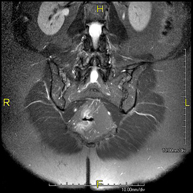

Prova diagnòstica no invasiva que consisteix en l'obtenció d'imatges d'alta definició anatòmica de la columna lumbar i sacre mitjançant l'ús d'un camp electromagnètic i ones de ràdio (amb un emissor i un receptor). No utilitza radiació ionitzant. Indicacions: traumatismes, ciàtica, hèrnies discals, tumors, infeccions - RM Mielografia

Prova diagnòstica no invasiva que consisteix en l'obtenció d'imatges d'alta definició anatòmica de la medul·la espinal i les arrels nervioses mitjançant l'ús d'un camp electromagnètic i ones de ràdio (amb un emissor i un receptor), així com seqüències d'estudi especials (mielogràfiques). No utilitza radiació ionitzant. Indicacions: hèrnies, compressions medul·lars. - RM de Plexe braquial